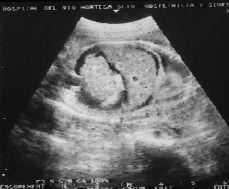

Ecográficamente se observa un polihidramnios moderado, el feto está hidrópico, con un derrame pleural bilateral y marcada ascitis. El líquido ascítico diseca el borde diafragmático y se aprecia hepatomegalia. Las asas intestinales están comprimidas formando un paquete (Fig. 1).

Figura 1.Ascitis fetal. Semana gestacional 31. Se observa el paquete intestinal comprimido, la hepatomegalia y el contorno diafragmático.